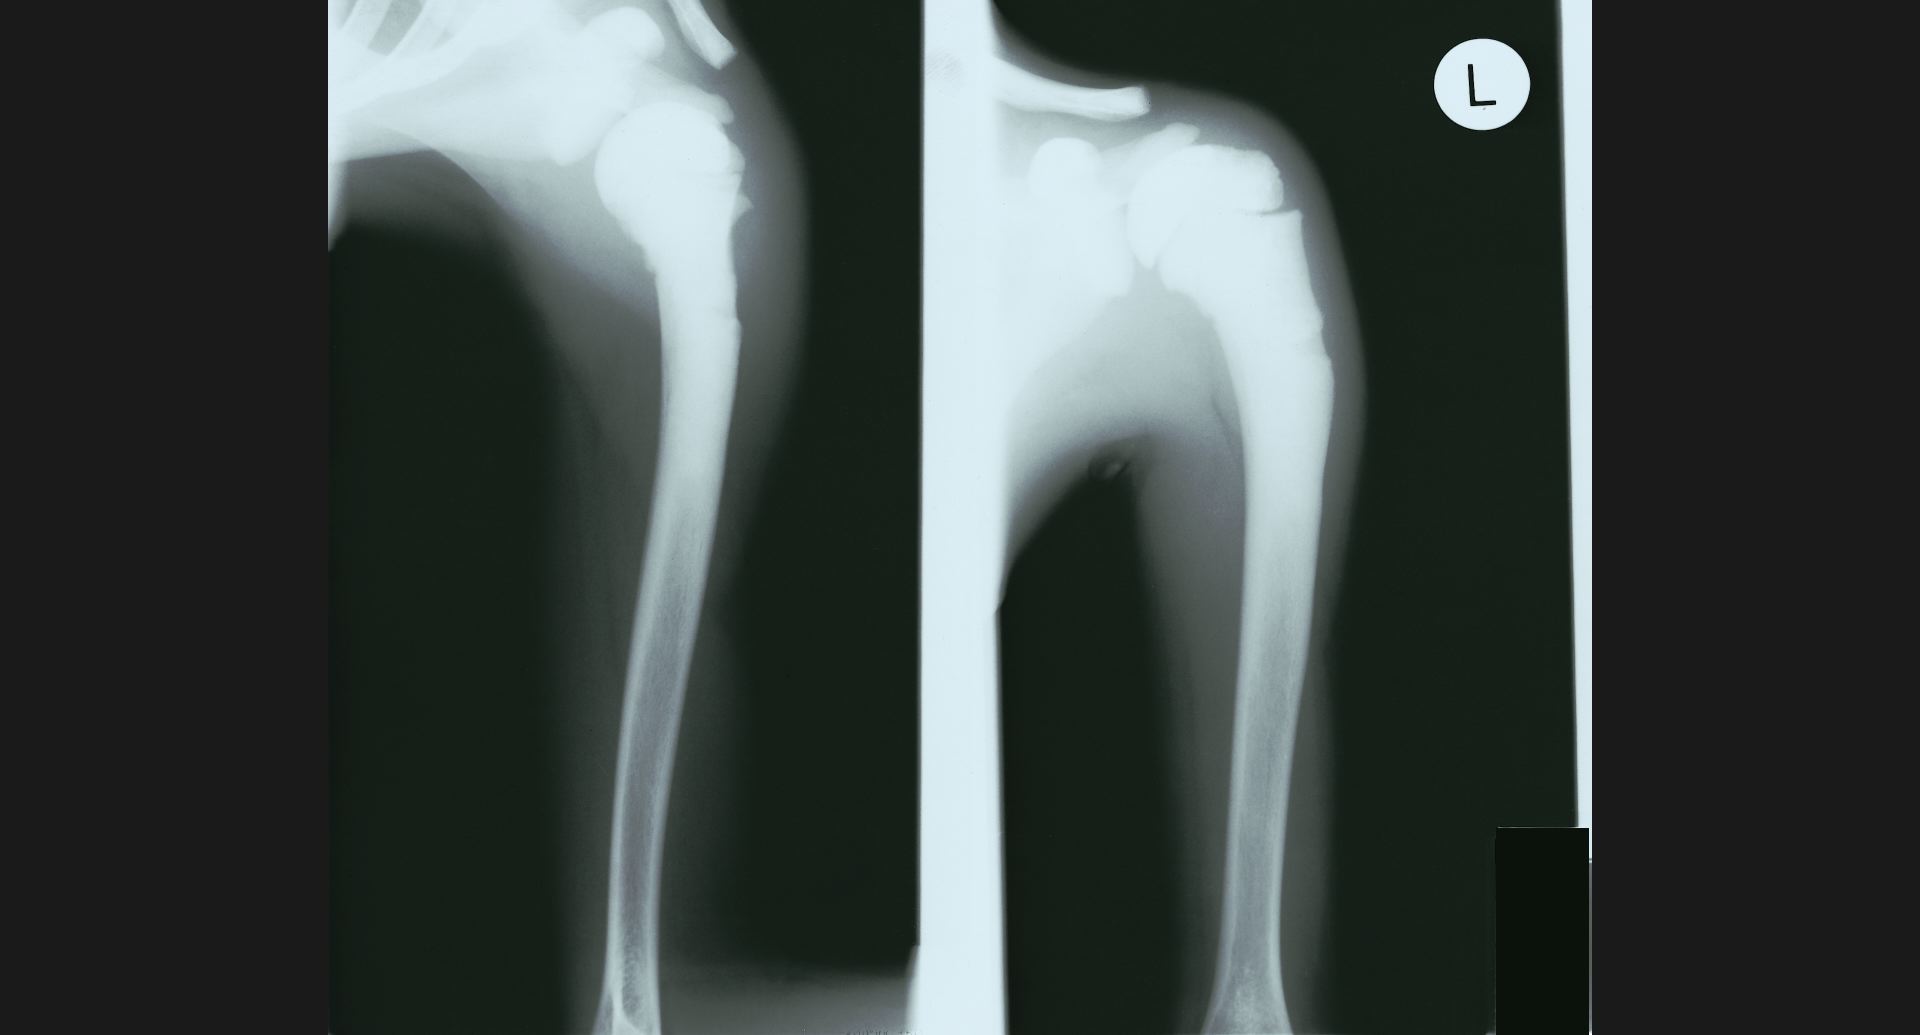

fig.15(55KB) :Fibrous dysplasia

骨頭のtrabeculation。病変部。